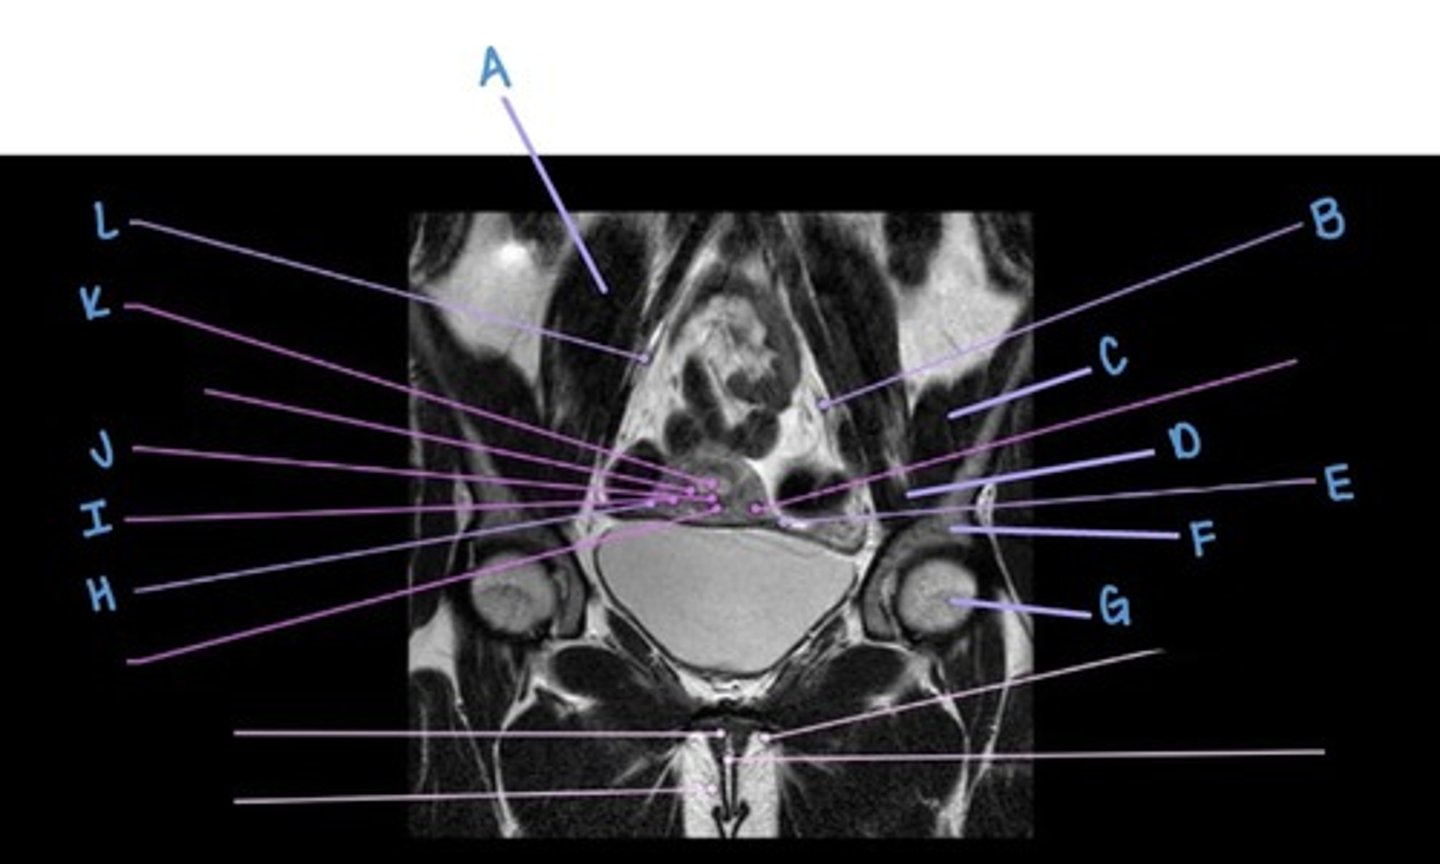

ilium

A

iliacus muscle

B

suspensory ligament of the ovaries

C

perimetrium

D

sigmoid colon

E

gluteus maximus muscle

F

ovary

G

gluteus medius muscle

H

myometrium

I

gluteus minimus muscle

J

endometrium

K

uterus

L